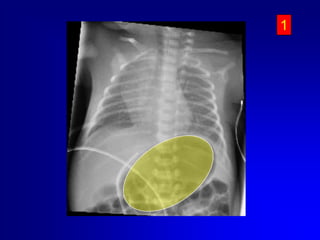

Eseguire sempre controllo radiografico o ecografico della posizione del catetere..

Il CVO può essere mantenuto per un tempo massimo di 14 giorni. Nei VLBW sarebbe preferibile rimuoverlo entro 7-8 giorniApplicare suzione lieve alla siringa.Se non vi è ritorno ematico vi può essere un coagulo sulla punta, quindi sfilare il catetere in aspirazione, rimuovere il cagulo e reinserire. Se vi è ritorno ematico, continuare ad inserire il catetere fino alla distanza stimata. Se il catetere incontra qualche ostruzione prima della distanza desiderata:Cause più comuniEntrato nel sistema portaleIncuneato in una branca intraepatica della vena ombelicaleRetrarre il catetere di 2-3 cm ruotarlo delicatamente e reinserirlo Se il catetere è nel circolo portale lasciare li il catetere; reinserire un altro 5–Fr nello stesso vaso. Una volta che il catetere è nella posizione giusta  si sfila quello in porta. Questa procedura ha successo nel 50% dei casi.

Eseguire semprecontrollo radiografico o ecografico della posizione del catetere..

Il CVO puòessere mantenuto per un tempo massimo di 14 giorni. Nei VLBW sarebbe preferibile rimuoverlo entro 7-8 giorniApplicare suzione lieve alla siringa.Se non vi è ritorno ematico vi può essere un coagulo sulla punta, quindi sfilare il catetere in aspirazione, rimuovere il cagulo e reinserire. Se vi è ritorno ematico, continuare ad inserire il catetere fino alla distanza stimata. Se il catetere incontra qualche ostruzione prima della distanza desiderata:Cause più comuniEntrato nel sistema portaleIncuneato in una branca intraepatica della vena ombelicaleRetrarre il catetere di 2-3 cm ruotarlo delicatamente e reinserirlo Se il catetere è nel circolo portale lasciare li il catetere; reinserire un altro 5–Fr nello stesso vaso. Una volta che il catetere è nella posizione giusta si sfila quello in porta. Questa procedura ha successo nel 50% dei casi.